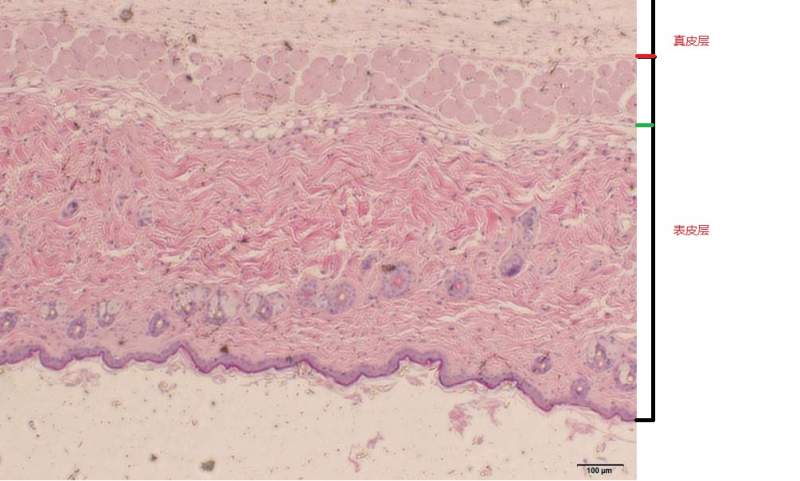

ÎÒÏë²âÁ¿Ð¡ÊóÕæÆ¤²ãºñ¶È£¬²»ÖªµÀÕæÆ¤²ãÊÇ´ÓÄĵ½ÄÄÀï¡£ÇëÔÚÎÒÉÏ´«µÄÕÕÆ¬ÉϱêעСÊ󯤷ôÕæÆ¤²ãÆðʼλÖã¡Ð»Ð»£¡ ʵB4 40.jpg ¿ÕA4 100.jpg |

ÎÒ²»È·¶¨ÊÇ´ÓºìÉ«¿ªÊ¼»¹ÊÇÂÌÉ«¿ªÊ¼£¬²»¹ý°´ÕÕÈËÀàÆ¤·ôµÄ»°£¬ÕæÆ¤²ã´ó²¿·ÖÓ¦¸ÃÊǽºÔµ°°×ÏËά£¬ËùÒÔ¹À¼ÆÊÇ´ÓºìÉ«¿ªÊ¼µÄ¿ÉÄÜÐÔ´ó w132h2020088_1394102873_568.jpg w132h2020088_1394102883_469.jpg |

ÖØÉú²½Ô¶: ½ð±Ò+8, ¡ïÓаïÖú, ÓÐÎÄÏ×ÖÐСÊóÕæÆ¤²ãºñ¶È´ó¸ÅÔÚ300¦Ìm×óÓÒ£¬Ó¦´ðÕß±ê×¢µÄÕæÆ¤²ãºñ¶È²»ÔÚ300΢Ã××óÓÒ¡£²»¹ý»¹ÊÇллÁË£¡ 2014-03-22 20:11:54